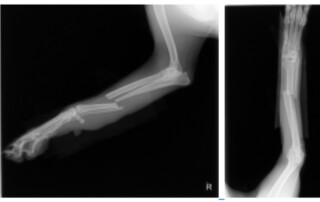

Thankfully, after what felt like an eternity, we found Thor. However, it quickly became apparent that he had been injured during his time away. We rushed him to the veterinarian, where he underwent surgery to address his broken leg.

Now, a couple of months later, Thor is still limping, and we’re concerned that his bone might not be healing properly. Despite our extensive Googling, we’re still not sure if he’s experiencing a bone malunion, but we’re doing everything we can to help him heal and recover.